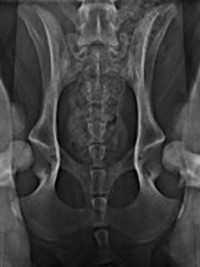

Le displasie possono essere diagnosticate precocemente con esami radiografici eseguiti dal quinto/sesto mese di vita. Questi esami, effettuati in sedazione, includono proiezioni specifiche per anca e gomito e sono essenziali per intervenire tempestivamente.

Nello specifico lo studio dell’anca prevede ben 4 proiezioni (antero posteriore standard, in distrazione, a rana e dar).

Lo studio del gomito prevede due proiezioni (latero /laterale e antero posteriore).